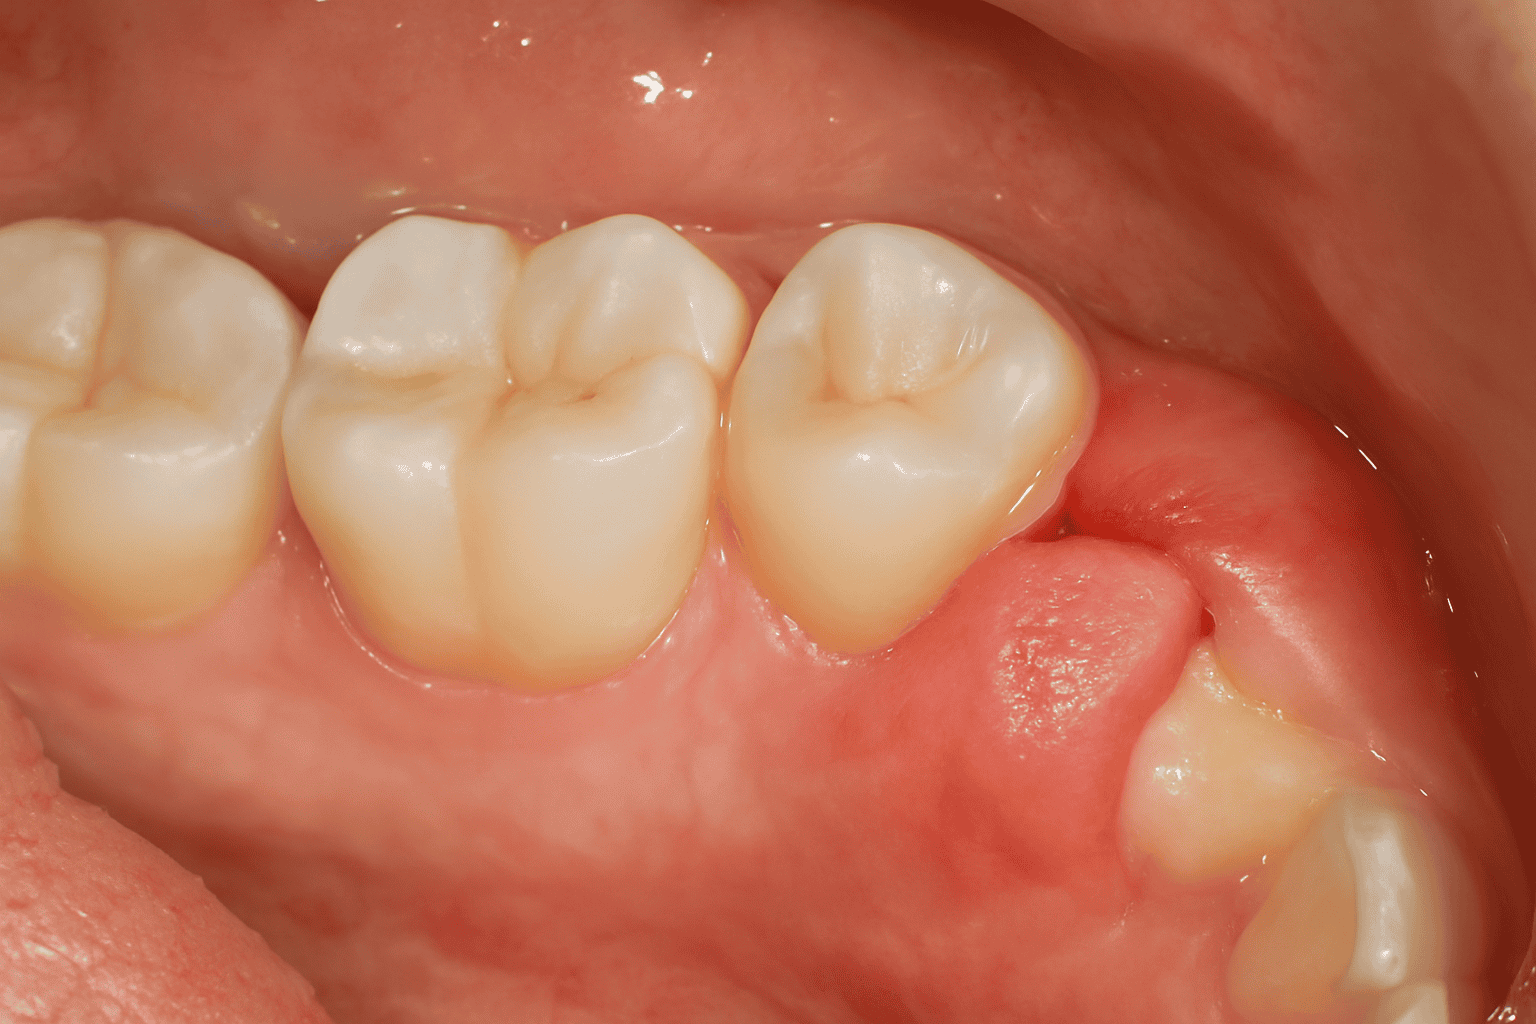

Pain and swelling

gingivitis

Treatment: Problematic wisdom teeth are often removed by surgical intervention.Wisdom teeth that are not impacted and have emerged properly can be monitored without being extracted.

Regular X-ray checkups are important for early detection of wisdom teeth condition.